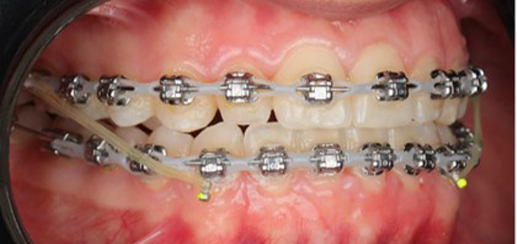

Initial leveling in the maxillary arch was carried out with a 0.014 CuNiTi archwire. This was followed by a 0.018 CuNiTi wire, with stoppers positioned mesial to the molars and activated to provide protrusion of incisors. The mandibular arch was then bonded and initial alignment was achieved with a 0.014 CuNiTi wire, then both jaws are progressing to 0.014 × 0.0275 CuNiTi and subsequently 0.018 × 0.0275 CuNiTi for torque control.

Finishing was completed with a 0.018 × 0.0275 TMA archwire in conjunction with Class III elastics.